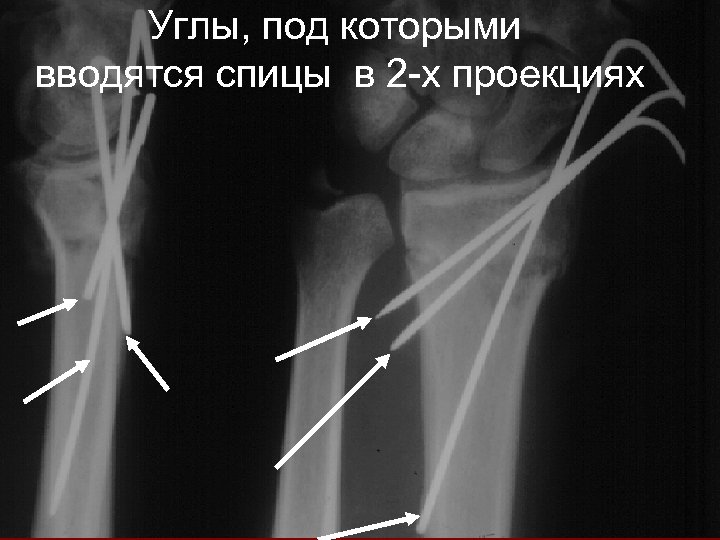

Углы, под которыми вводятся спицы в 2 -х проекциях

КЛЮЧЕВЫЕ МОМЕНТЫ • Сначала - репозиция • Используйте спицы Киршнера 1, 6 мм • 3 спицы проходят через 2 кортикальных слоя • Тест удаления спиц (“PINCH” TEST) • Наличие ЭОПа

Определение точек введения спиц